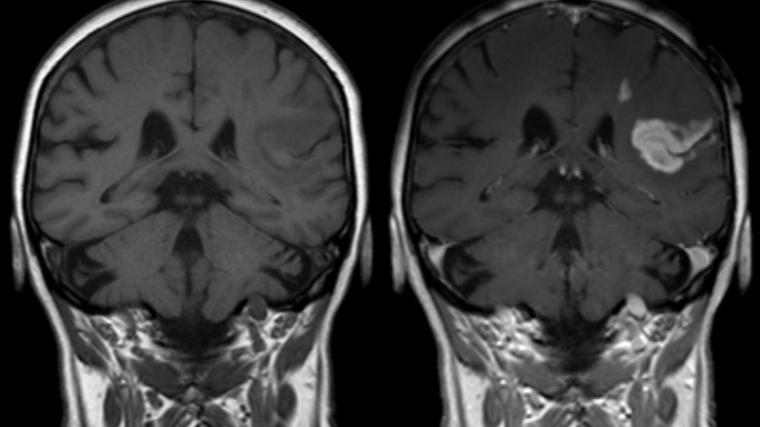

Un accidente cerebrovascular (ACV) es la aparición súbita de síntomas neurológicos como resultado de una interrupción del flujo sanguíneo. Sin la sangre que suministra el oxígeno y los nutrientes a las neuronas, éstas empiezan a morir de forma muy rápida. Este puede darse también como consecuencia de diferentes trastornos vasculares.

El ACV es la causa de muerte más frecuente en todo el mundo y sus consecuencias dependen del lugar y el tamaño de la lesión.

Si se interrumpe el flujo a través de pequeños vasos sanguíneos las consecuencias pueden ser menos graves que si se dan en grandes vasos. Por otro lado, si queda afectada una parte limitada de un vaso, el pronóstico es mejor que si quedan afectados vasos débiles o enfermos. En los casos más graves, un accidente cerebrovascular puede causar parálisis, deterioro del habla, pérdida de memoria y de la capacidad para razonar, coma o incluso la muerte.